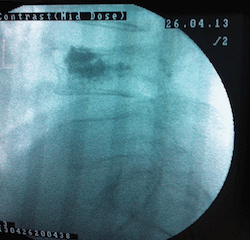

Hastaya uygulama öncesi sakinleştirci ilaç uygulanır. Hasta yüz üstü pozisyonda ameliyat masasına yatırılır. Omurga kırığının yerine göre sırt veya bel bölgesinde girişimin yapılacağı yer steril olarak silinip örtülür. Skopi(X-ışınları kullanarak görüntüleme sağlayan cihaz) kontrolü ile müdahalenin yapılacağı bölge görüntülenir .Girişim noktası saptandıktan sonra giriş noktasına lokal anestezik uygulanır. Bu noktadan küçük bir kesi yapılarak vertebroplasti iğnesi kemikle temas edene kadar ilerletilir ve iğne döndürülerek omurga korteksinin içine girilir. İğne yerleştirildikten sonra sıra kemik çimentosu skopi kontrolü ile sement verilir